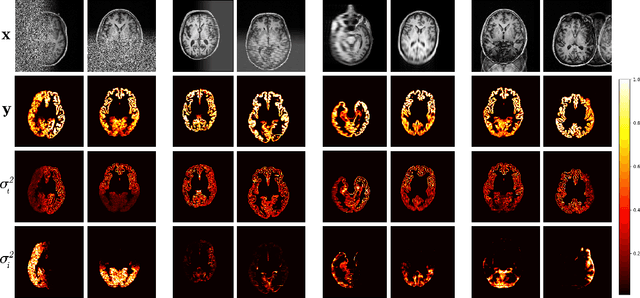

Abstract:Quality control (QC) of MR images is essential to ensure that downstream analyses such as segmentation can be performed successfully. Currently, QC is predominantly performed visually and subjectively, at significant time and operator cost. We aim to automate the process using a probabilistic network that estimates segmentation uncertainty through a heteroscedastic noise model, providing a measure of task-specific quality. By augmenting training images with k-space artefacts, we propose a novel CNN architecture to decouple sources of uncertainty related to the task and different k-space artefacts in a self-supervised manner. This enables the prediction of separate uncertainties for different types of data degradation. While the uncertainty predictions reflect the presence and severity of artefacts, the network provides more robust and generalisable segmentation predictions given the quality of the data. We show that models trained with artefact augmentation provide informative measures of uncertainty on both simulated artefacts and problematic real-world images identified by human raters, both qualitatively and quantitatively in the form of error bars on volume measurements. Relating artefact uncertainty to segmentation Dice scores, we observe that our uncertainty predictions provide a better estimate of MRI quality from the point of view of the task (gray matter segmentation) compared to commonly used metrics of quality including signal-to-noise ratio (SNR) and contrast-to-noise ratio (CNR), hence providing a real-time quality metric indicative of segmentation quality.